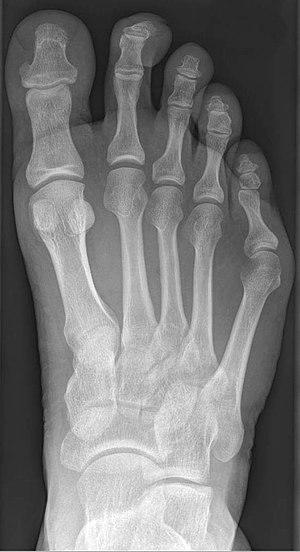

Radiograph showing a tailor's bunion

Tailor's bunion is easily diagnosed because the protrusion is visually apparent. X-rays may be ordered to help the surgeon find out the severity of the deformity.